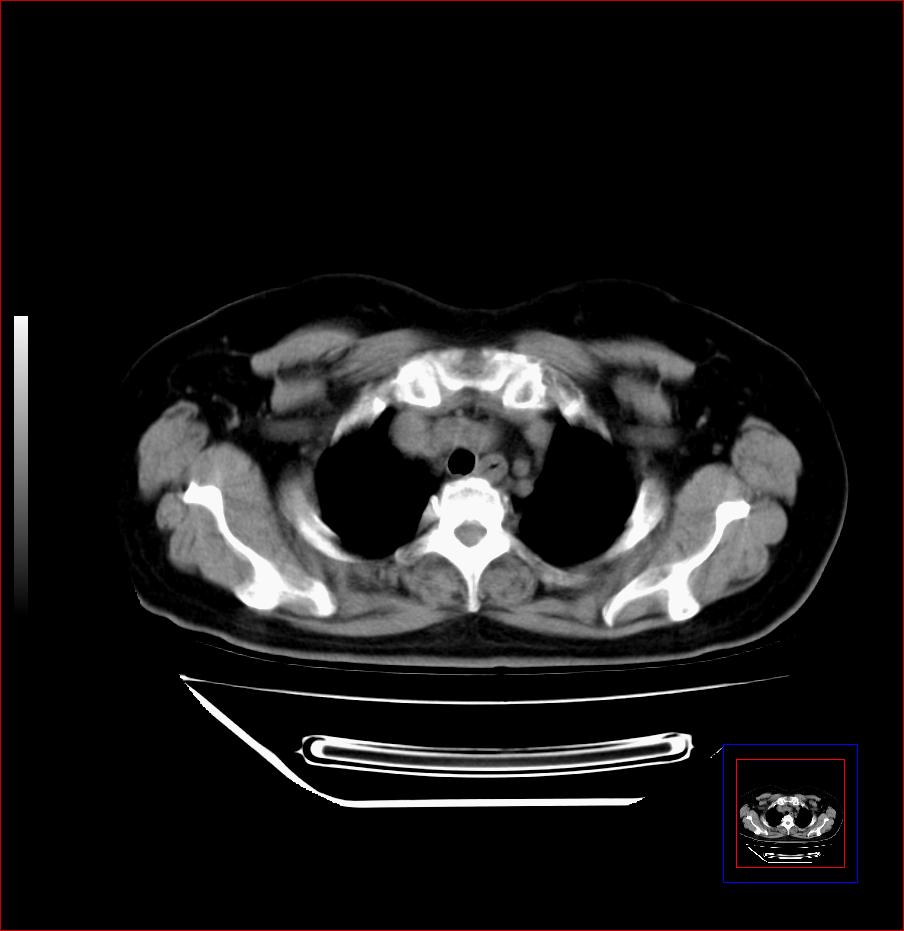

标题: CT25445:上段食管正常吗?

女,56岁,胸部体检,无不适。感觉食管壁略厚,最后约6mm.谢谢大家讨论,主要是自己亲人,疑神疑鬼的。主动脉弓旁淋巴结还有点肿大。